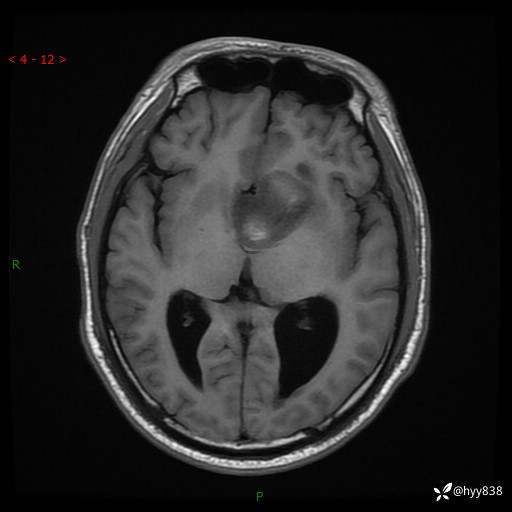

颅脑MRI平扫+增强